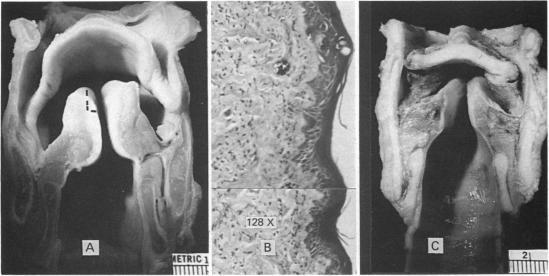

Proceedings of the anatomical society of great britain and ireland, july 1986.

J Anat. 1986 Dec;149:209-48.

17103595

https://pmc.ncbi.nlm.nih.gov/articles/PMC1261653/